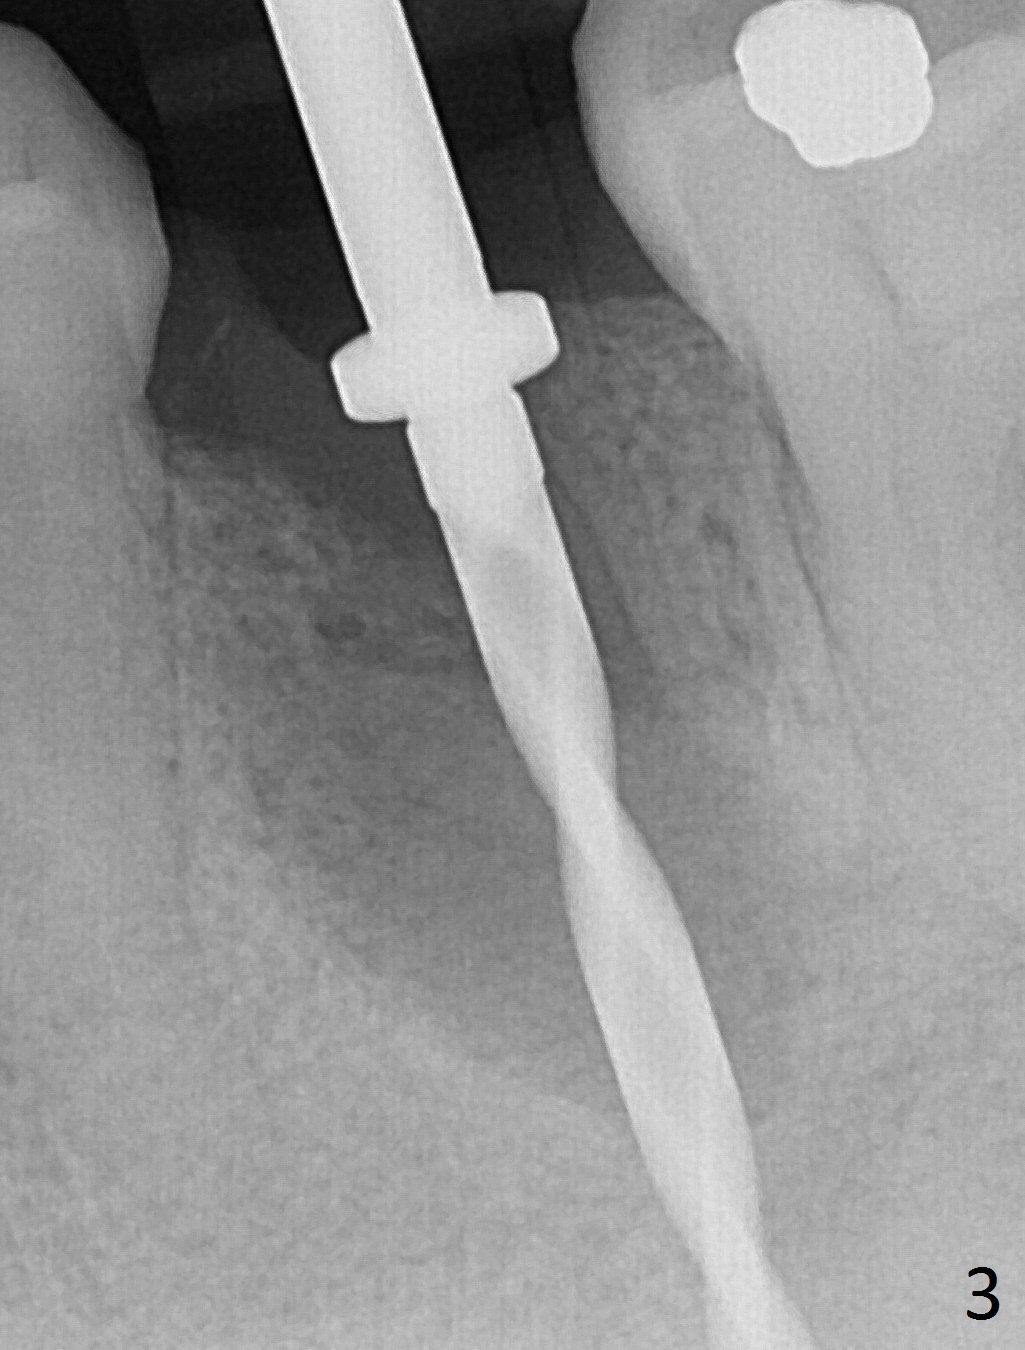

Extraction of the lower left 2nd premolar with vertical fracture (Fig.1,2 >) is easy because of peri-radicular radiolucency. The apical end of the osteotomy is not shown with a 2 mm pilot drill (Fig.3) or a 3.8x18 mm implant (Fig.4) in place. It appears that the implant is not placed deep enough. Following 3-4 more turns of the implant and placement of a 5.5x4(3) mm abutment (Fig.5 A), allograft is placed (*). A postop panoramic X-ray is taken (Fig.6); the osteotomy could have been deepened to reduce the possibility of periimplantitis. Retrospectively, the panoramic X-ray should be taken after use of the pilot drill. The bone around the implant appears to have regenerated 4 months postop (Fig.7,8). Bone density appears to continue increasing 9 months postop (i.e., 4.5 months post cementation, Fig.9). Bone loss is minimal 2 years post cementation (Fig.10).